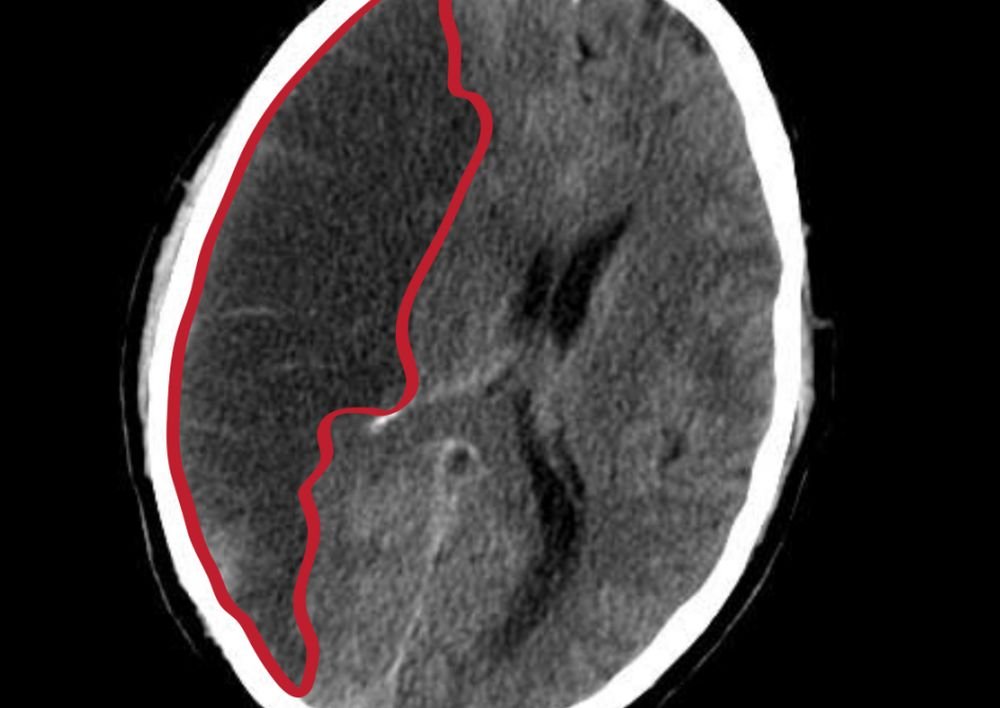

С помощью технологии искусственного интеллекта можно рассчитать личный риск человека столкнуться с еще одним инсультом. К такому выводу пришли исследователи из Университета Vall d' Hebrón в Испании.

Пациенты после инсульта могут проходить через анализ на искусственном интеллекте, который более персонализировано и тщательно рассчитает у них риск возможного рецидива. Повторные инсульты довольно часто оказываются фатальными, как показывает практика. Эксперты полагают, что исследование поможет определить наиболее важные факторы в деле предотвращения рецидивов инсультов, у него есть потенциал предотвращать многие тысячи острых нарушений мозгового кровообращения в Европе, а значит, предотвращать смерти и инвалидность.

Статистика показывает, что приблизительно 25% переживших инсульт пациентов сталкиваются с ещё одним, и до 80% этих рецидивов можно было бы предотвратить за счёт изменений в образе жизни и специально подобранного лечения. Количество проживающих с инсультом людей на территории Евросоюза с 2017 по 2047 год, как предполагается, вырастет на 27%. Преимущественно, это связано с увеличением количества европейцев старше 70 лет.

Исследователи для своих расчетов использовали неизменяемые факторы риска вроде возраста и этнического происхождения, а также изменяемые факторы риска образа жизни и привычки вроде курения, неправильного питания, повышенного артериального давления, показатели холестерина, уровня физической активности и некоторые другие социально-экономические особенности. На основе всей этой обширной информации искусственный интеллект и определял вероятность риска повторного инсульта в течение следующих трех месяцев, одного года и после года, пишет medicalxpress.com.